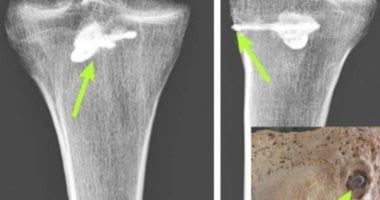

فحص رفات رجل جريح مغروز فى ساقه رأس سهم عمره 2000 عام فى إيران

كان البارثيون معروفين لدى الرومان بمهاراتهم في الحرب على الخيول والرماية وتشغيل المعادن، بما في ذلك تصنيع الأسلحة عالية الجودة، وقد دُفن هذا الرجل على جانبه الأيسر وساقاه مثنيتان فى وضعية منحنية. من بين متعلقاته الجنائزية بعض القطع الأثرية المعدنية والفخارية، بما في ذلك جرة اشتهرت بسوء بنائها وقدرت...